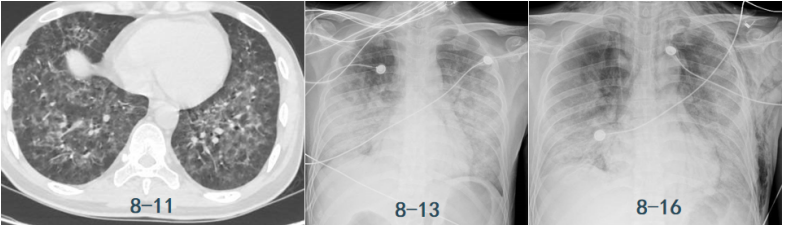

患者,女,50岁;活动后喘息20天,加重伴发热3天,2021年11月19日转入我院。入院胸部CT显示:双肺实变,磨玻璃影(图1)。11月24日复查胸部CT可见病变进展迅速(图2)。予患者气管插管机械通气、俯卧位等,呼吸衰竭未见改善。遂于11月25日启动VV-ECMO(转速2860 rpm,流量4.5 L/min,氧浓度100%)。追问病史:患者入院前1月有活动后气促症状,自觉全身不适,近2年有眼干、口干不适。进一步检查发现,ANA反应阳性(+),ANA核型为胞浆颗粒型(异常);抗SSA/Ro抗体阳性(++)、抗Ro-52抗体阳性(+++)。诊断:急性间质性肺炎(AIP);Ⅰ型呼吸衰竭;混合性结缔组织病。治疗:VV-ECMO+呼吸机辅助通气+俯卧位通气、激素(甲强龙80 mg×7天,60 mg×3天,40 mg qd)、免疫抑制剂(环磷酰胺400 mg qd×3天)、抗感染(哌拉西林他唑巴坦4.5 g q12h+莫西沙星0.4 g qd+氟康唑氯化钠注射液20 mg qd)、抗凝等。在随后的一段时间内,患者影像学改善不明显(图3)。直至12月20日,复查胸部CT可见患者肺部病变较前明显吸收(图4)。2021年12月31日VV-ECMO撤机后,继续气切呼吸机辅助通气,甲强龙40 mg qd抗炎治疗,继续抗感染治疗,2022年1月7日脱机,1月21日气管封管,1月26日出院。后续治疗:强的松25 mg qd,环磷酰胺600 mg q2w×4次,序贯吗替麦考酚酯0.5 g bid。重症间质性肺疾病(ILD)在诊断方面需要考虑以下问题:是ILD吗?是哪种ILD?严重程度如何?在治疗方面,除了生命支持(呼吸支持重点)和病因治疗,并发症的处理也至关重要。重症ILD的诊断包括两方面,一方面是通过影像学、病史+临床表现、BALF-NGS、实验室检查、肺活检等对ILD进行诊断;另一方面涉及重症,患者多面临呼吸衰竭甚至多器官衰竭,因此时间更加紧迫。在ICU内最常见的重症ILD包括:特发性肺纤维化急性加重(AE-IPF)、自身免疫相关性ILD、肿瘤治疗相关性ILD、隐源性机化性肺炎(COP)、AIP、过敏性肺炎(HP)、急性嗜酸性粒细胞性肺炎(AEP)、药物相关ILD等。在影像学方面,最易导致重症的类型有弥漫性磨玻璃影和实变影。最常见的鉴别诊断就是重症肺部感染。表现为弥漫性磨玻璃影或实变影的ILD较为多见,例如:HP、嗜酸性粒细胞性肺炎(EP)、结缔组织病相关间质性肺病(CTD-ILD)、非特异性间质性肺炎(NSIP)、脱屑性间质性肺炎(DIP)、淋巴细胞性间质性肺炎(LIP)、机化性肺炎(OP)、AE-IPF、肺泡蛋白沉积症(PAP)、肺泡微结石症、结节病、弥漫性肺泡出血综合征、肺水肿等。而很多感染性疾病影像学也可表现为磨玻璃影,例如:卡氏肺孢子菌肺炎(PCP)、病毒性肺炎、巨细胞病毒性肺炎、支原体肺炎。尽管如此,ILD也有部分影像学具有特征性,可以被识别。图5左表现为肺陷闭,也称为“猪头肉冻征”,这是典型的亚急性HP的影像学特征。图5右表现为弥漫性磨玻璃影,但以肺门向外扩展,外面有肺大泡,这是典型的PCP表现。临床上多见自身免疫性疾病导致的ILD,此类疾病也具有共同的特征,例如双肺弥漫,病理方面以NSIP或OP为主要特征。但也有部分患者可以出现弥漫性肺泡损伤(DAD)特征。如图6所示,左图为ANCA相关性血管炎,右图为MDA5相关性间质性肺病。因此,一定要警惕容易发生这种病理改变的自身免疫性疾病。